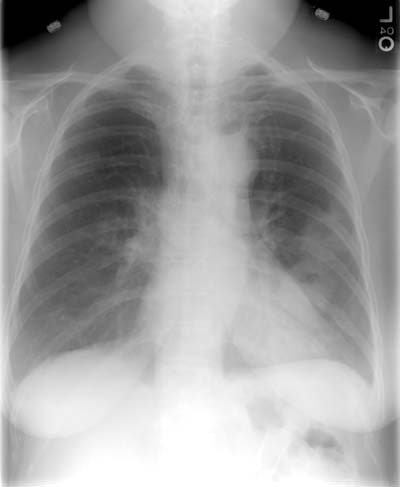

Nocardia Pulmonary Infection- Case 2

The patient was receiving high doses of corticosteroids when the developed symptoms of

pulmonary infection. Multiple, thick walled cavitary nodules can be seen. Bronchoscopy was

performed and cultures grew Nocardia. CXR and CT scan are shown below.

(Click CXR for larger image)